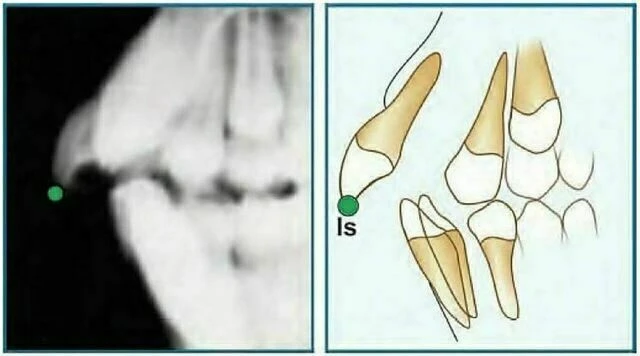

Incision Superius (Is) : Đỉnh rìa cắn của răng cửa giữa hàm trên nằm về phía ngoài nhất.